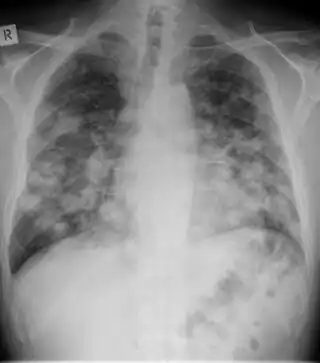

Chest X-ray of lungs affected by histoplasmosis -